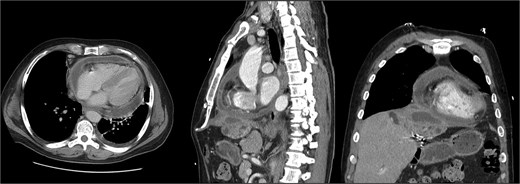

He was seen in the clinic 6 days later. At that time, he reported worsening abdominal pain and orthopnea. Repeat imaging showed that the hepatic abscess was stable in size, but the pericardial effusion had worsened and that the hepatic abscess had broken through the right hemidiaphragm (Fig. 4). Given his multiple instances of failed management, HPB Surgery elected to perform diagnostic laparoscopy. A TTE was performed, which showed a loculated pericardial effusion. Cardiothoracic Surgery (CTS) was consulted to see if drainage was indicated. They deemed that a pericardial window was needed, but it would depend on the outcome of the hepatic abscess drainage.

Second readmission imaging—CT of the chest in the axial, sagittal, and coronal views. These demonstrate that the abscess has eroded through the diaphragm and now abuts the pericardium. Additionally, it shows a worsening of the pericardial effusion, concerning for abscess communication.